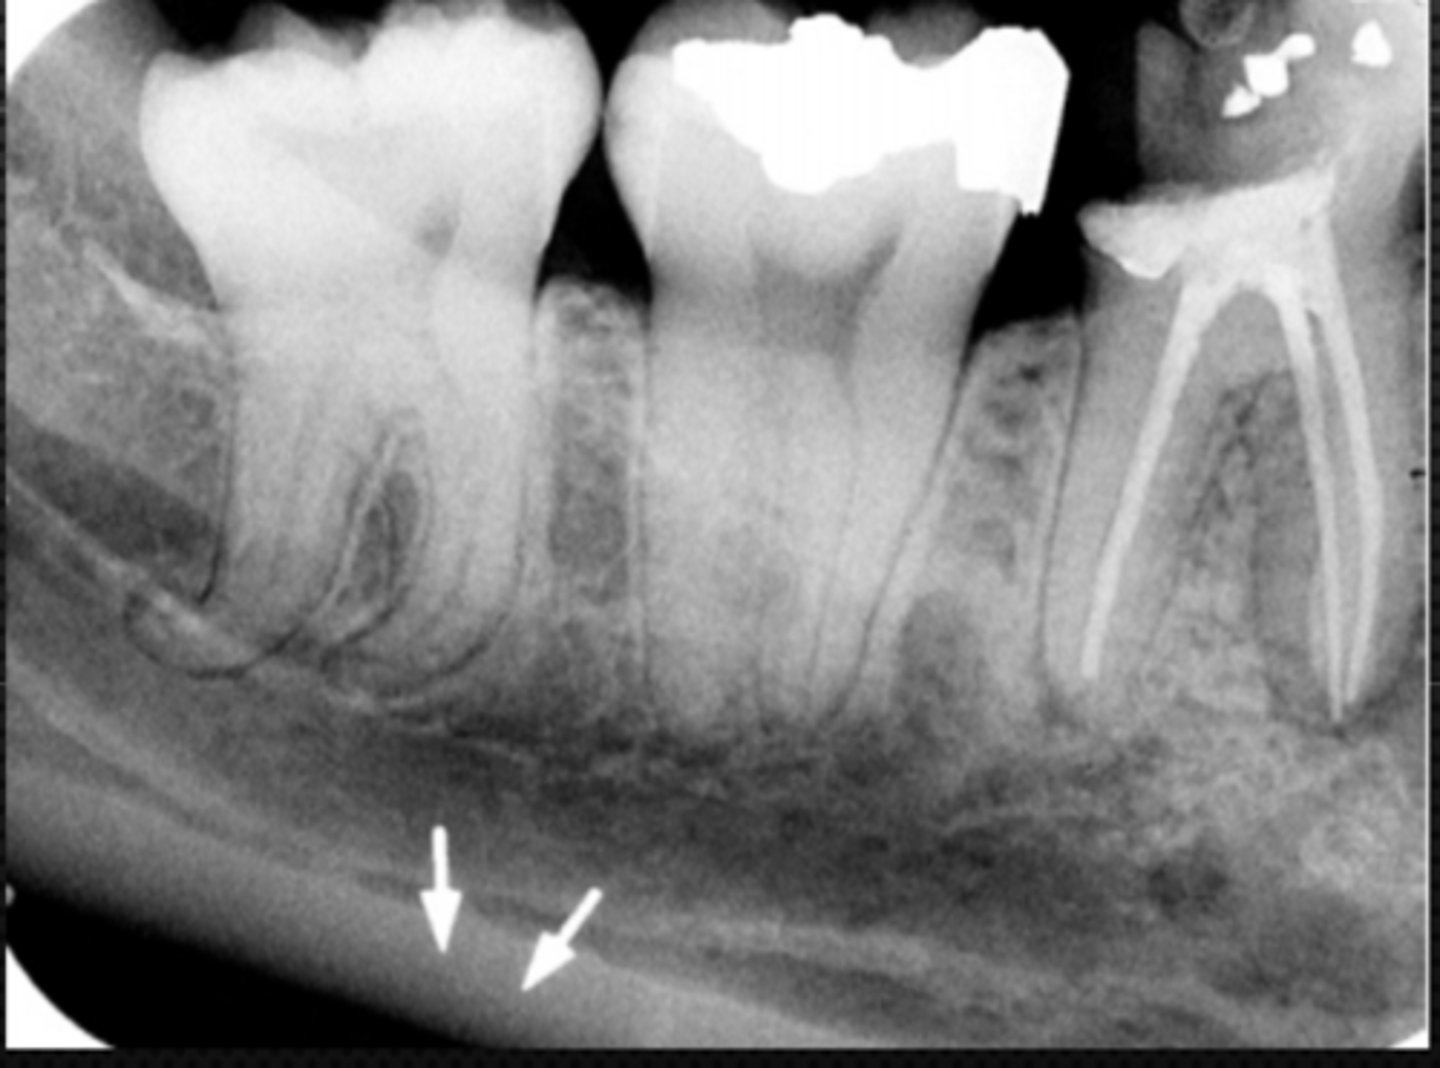

28

Mandibular canal

Identify the structure

29

Identify the radiolucent structure

30

Nutrient canals (neurovascular canals)

32

External oblique ridge

33

Mylohyoid (internal oblique) ridge

Identify the radiopaque structure

34

Submandibular fossa

Identify the large radiolucent area